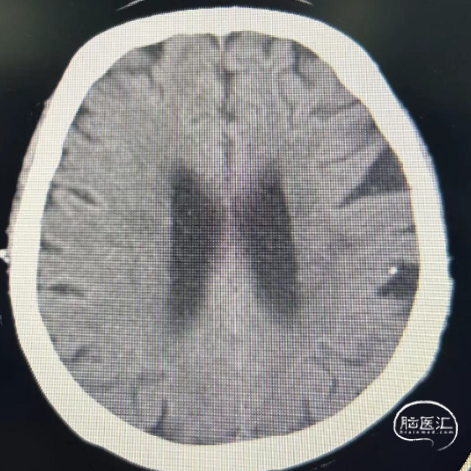

随访:患者术后CT复查,一般情况好,神经系统查体无明显异常,血压控制良好。